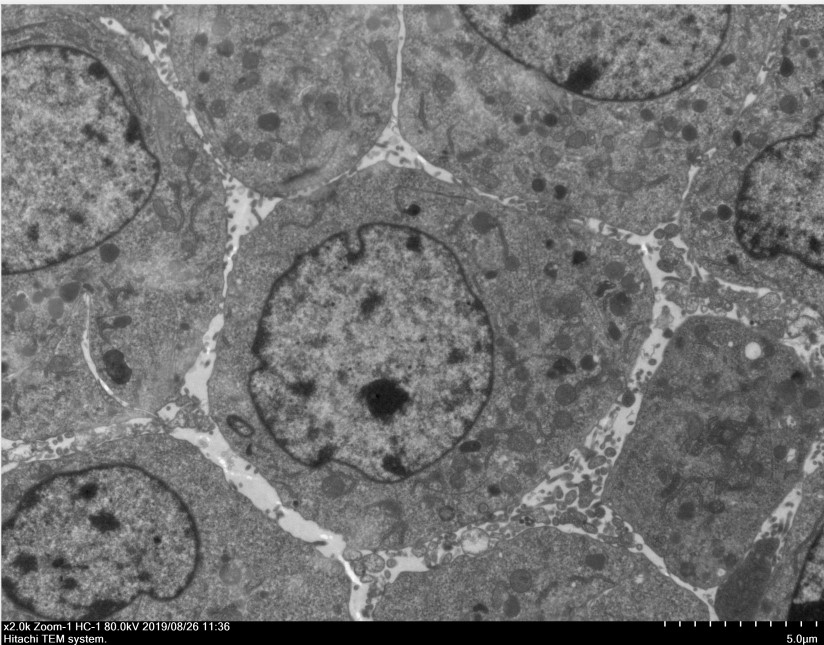

透射電鏡,即透射電子顯微鏡(TEM),電子束在穿過樣品時(shí),會(huì)和樣品中的原子發(fā)生散射,樣品上某一點(diǎn)同時(shí)穿過的電子方向是不同,這樣品上的這一點(diǎn)在物鏡1-2倍焦距之間,這些電子通過過物鏡放大后重新匯聚,形成該點(diǎn)一個(gè)放大的實(shí)像,可以看到在光學(xué)顯微鏡下無法看清的小于0.2um的超微結(jié)構(gòu),主要應(yīng)用于物質(zhì)內(nèi)部的超微結(jié)構(gòu)觀察。

四、成果展示